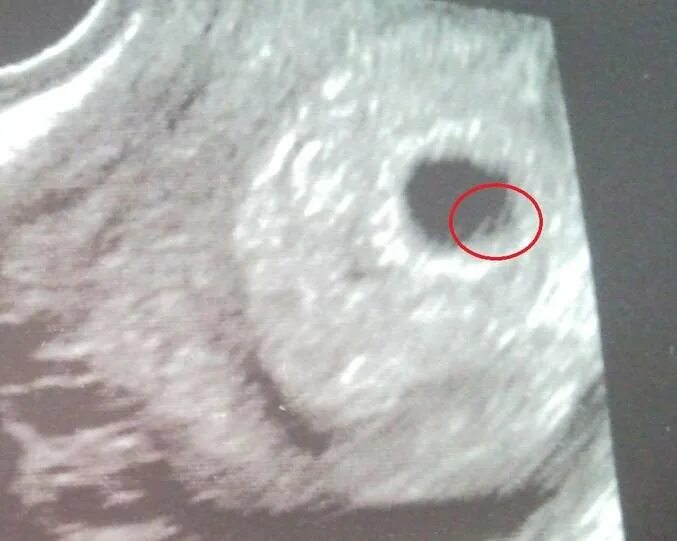

Желточный мешок есть а эмбриона нет